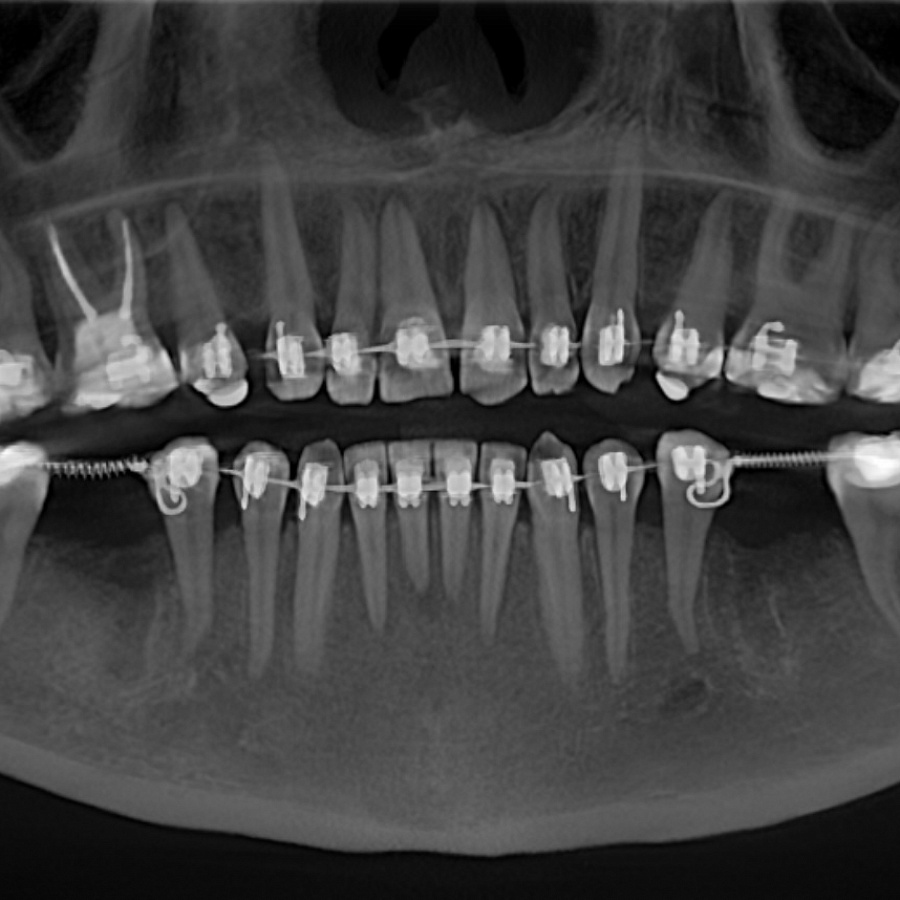

Пациентка начала ортодонтическое лечение и за 5 месяцев до окончания лечения ей удалили нижние шестерки и поставили импланты. За месяц до конца лечения установили формирователи десны. На момент снятия брекетов были сняты слепки под постоянные коронки на имплантатах.

В этом случае одновременно пациент закончил ортодонтическое, хирургическое и ортопедическое лечение. Что возможно только при одновременном подходе команды врачей.